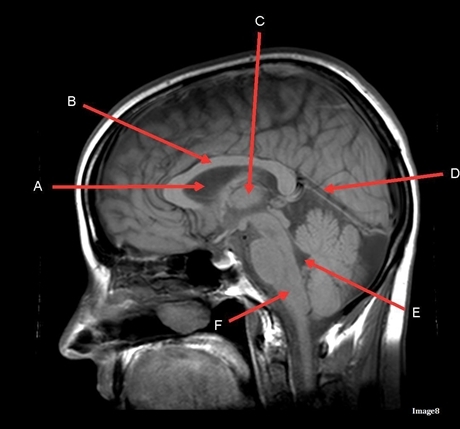

Image weighting and axis

T1 Sagittal

A

Lateral Ventricle

B

Corpus Callosum

C

Thalamus

D

Tentorium

E

4th Ventricle

F

Medulla Oblongata